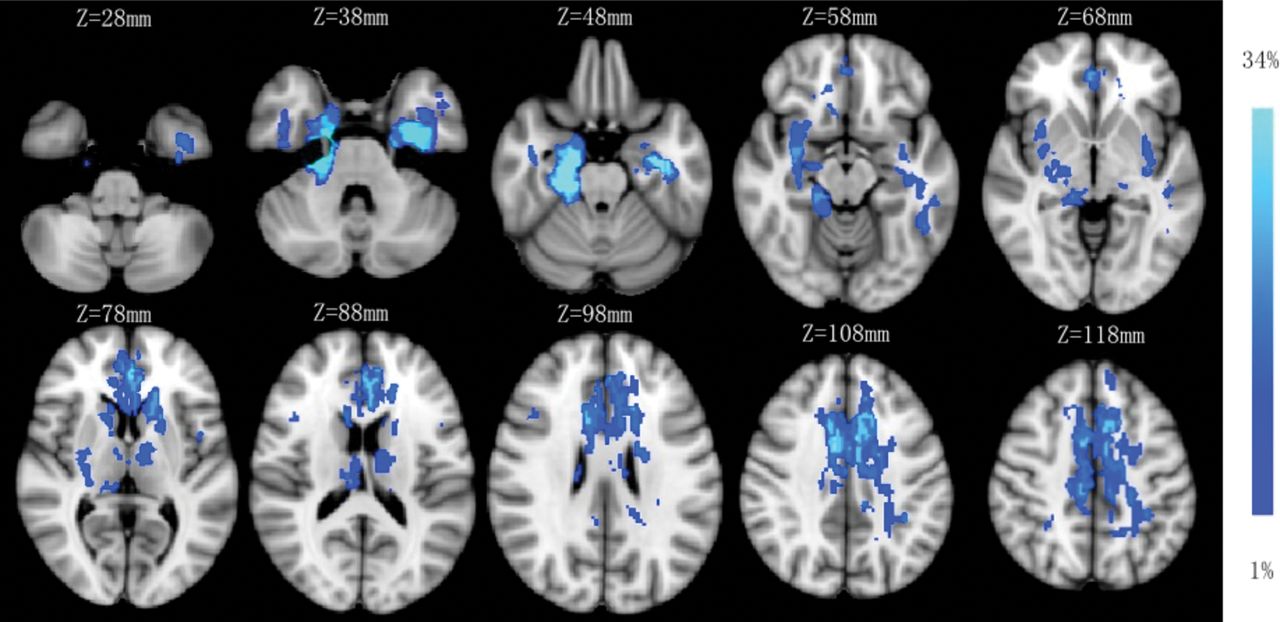

Lesion probability map of brain MR imaging. The mean lesion probability distribution thresholded at 34% is shown in light blue and thresholded at 1% is shown in blue and overlaid on the ICBM152 T1 template in the Montreal Neurological Institute space.